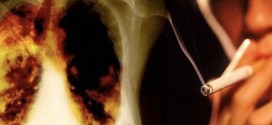

CANCER PULMONAR NO MICROCITICO

El cáncer pulmonar no microcítico (CPNM). Los pulmones son dos órganos con apariencia de esponja que se encuentran en su pecho. El pulmón derecho se divide en tres secciones, denominadas lóbulos. Su pulmón izquierdo tiene dos lóbulos. El pulmón izquierdo es más pequeño debido a que el corazón ocupa más espacio en ese lado del cuerpo. Cuando usted respira, el …